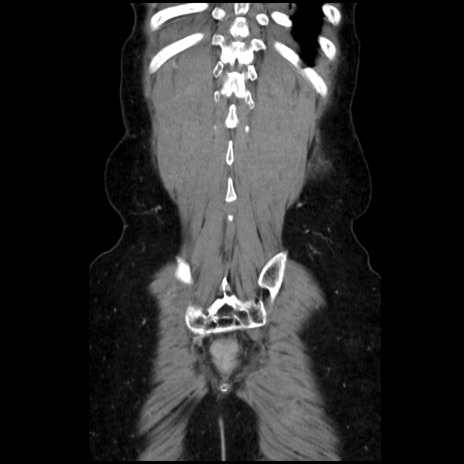

症例32(冠状断像)

【症例】40歳代 女性

【主訴】上腹部痛、嘔気・嘔吐

【現病歴】約9時間前頃から急に上腹部痛、嘔気、嘔吐が出現。改善しないため救急要請。

【既往歴】子宮頚癌(広汎子宮全摘術、放射線療法)、腸閉塞

【身体所見】腹部:平坦、軟、腸雑音亢進、上腹部を中心に腹部全体に圧痛あり。

【データ】WBC 8400、CRP 0.03